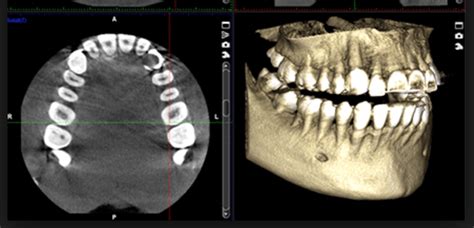

- TAC 3D: Para un diagnóstico preciso desde el primer día y un seguimiento óptimo de los tratamientos.

| TAC 3D | Diagnóstico preciso y seguimiento óptimo |